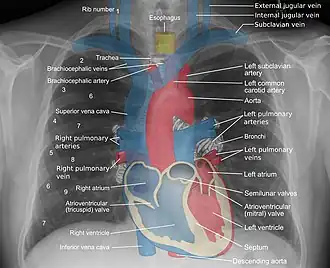

Landmarks

In the average person, the diaphragm should be intersected by the 5th to 7th anterior ribs at the mid-clavicular line, and 9 to 10 posterior ribs should be viewable on a normal PA inspiratory film. An increase in the number of viewable ribs implies hyperinflation, as can occur, for example, with obstructive lung disease or foreign body aspiration. A decrease implies hypoventilation, as can occur with restrictive lung disease, pleural effusions or atelectasis. Underexpansion can also cause interstitial markings due to parenchymal crowding, which can mimic the appearance of interstitial lung disease. Enlargement of the right descending pulmonary artery can indirectly reflect changes of pulmonary hypertension, with a size greater than 16 mm abnormal in men and 15 mm in women.[6]

Appropriate penetration of the film can be assessed by faint visualization of the thoracic spines and lung markings behind the heart. The right diaphragm is usually higher than the left, with the liver being situated beneath it in the abdomen. The minor fissure can sometimes be seen on the right as a thin horizontal line at the level of the fifth or sixth rib. Splaying of the carina can also suggest a tumor or process in the middle mediastinum or enlargement of the left atrium, with a normal angle of approximately 60 degrees. The right paratracheal stripe is also important to assess, as it can reflect a process in the posterior mediastinum, in particular the spine or paraspinal soft tissues; normally it should measure 3 mm or less. The left paratracheal stripe is more variable and only seen in 25% of normal patients on posteroanterior views.[7]

Localization of lesions or inflammatory and infectious processes can be difficult to discern on chest radiograph, but can be inferred by silhouetting and the hilum overlay sign with adjacent structures. If either hemidiaphragm is blurred, for example, this suggests the lesion to be from the corresponding lower lobe. If the right heart border is blurred, than the pathology is likely in the right middle lobe, though a cavum deformity can also blur the right heard border due to indentation of the adjacent sternum. If the left heart border is blurred, this implies a process at the lingula.[8]